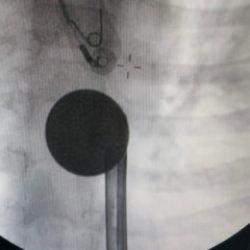

Bocavirüsü, direkt normal testlerle tanıyamadıklarını anlatan Doç. Dr. Özge Metin Akcan, "PISA dediğimiz ayrıntılı moleküler testlerimizle tanıyabiliyoruz. Diğer solunum yolu virüsüne benzer şekilde, yine ortam havalandırması, öksürürken dikkat edilmesi, ellerin yıkanması gibi önlemlerin alınması gerekiyor. Spesifik tedavisi yok, yani özel bir tedavisi yok. Bir destek tedavisi vermemiz gerekiyor. Hasta kötüyse, yatırmamız gerekiyor ve yatırdıktan sonra da solunum desteğini sağlamamız gerekiyor. Sıvı alamıyorsa, beslenemiyorsa, bunların desteğini sağlamamız gerekiyor. 2 yaşın altındaki çocuklarda, özellikle ağırsa solunum yolu enfeksiyonu, hatta ölümle sonuçlanabilen solunum yolu enfeksiyonlarına neden olabiliyor. Diğer virüsler de aslında benzer şekilde kliniklere sebep olabiliyor ama özellikle bu bocavirüs dedirtecek bir klinik tablomuz yok; dediğimiz gibi, biz bunları ayrıntılı solunum tetkikleri alıp öyle değerlendiriyoruz ve diğer hastalarda da benzer şekilde yaklaşıyoruz" ifadelerini kullandı.